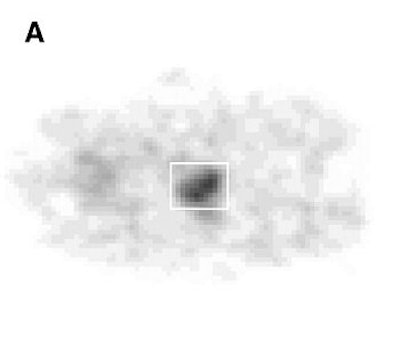

| Histopathologic correlation of F-18 fluorocholine PET of prostate. (A) One-hour delayed PET scan of pelvis of subject 14 shows increased F-18 fluorocholine uptake in prostate (enclosed by white box). Kwee SA, Wei H, Sesterhenn I, Yun D, Coel MN, "Localization of Primary Prostate Cancer with Dual-Phase 18F-Fluorocholine PET" (Journal of Nuclear Medicine, Vol. 47, No. 2, 262-269). Reprinted by permission of SNM. |